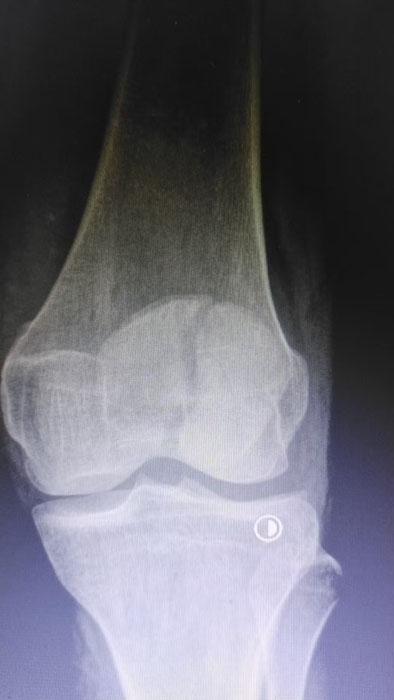

該患者因意外外傷導(dǎo)致髕骨骨折后,緊急前往何店鎮(zhèn)中心衛(wèi)生院就診。該院外科醫(yī)護(hù)團(tuán)隊(duì)迅速響應(yīng)、規(guī)范處置,第一時間為患者完善各項(xiàng)術(shù)前檢查,全面細(xì)致評估患者身體狀況及骨折傷情,精準(zhǔn)把握手術(shù)指征。為最大限度保障手術(shù)安全與治療效果,切實(shí)減少患者往返城區(qū)醫(yī)院的奔波之苦,降低就醫(yī)成本,該院立即啟動醫(yī)共體專家協(xié)作機(jī)制,正式向曾都區(qū)人民醫(yī)院申請專家技術(shù)支持。接到申請后,徐三軍主任快速響應(yīng)、主動下沉,帶著豐富的臨床經(jīng)驗(yàn)和精湛的手術(shù)技術(shù)趕赴衛(wèi)生院,與該院外科醫(yī)護(hù)團(tuán)隊(duì)深入研討,結(jié)合患者具體病情制定個性化手術(shù)方案,細(xì)致梳理術(shù)前各項(xiàng)準(zhǔn)備工作,為手術(shù)順利開展筑牢堅(jiān)實(shí)基礎(chǔ)。